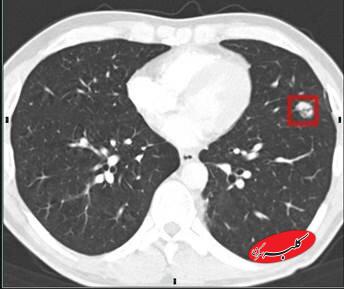

به گزارش همشهری آنلاین متخصصان میگویند غربالگری سرطان ریه اکنون به قدرتمندترین ابزار برای کاهش مرگ و میر ناشی از سرطان ریه بدل شده است. این غربالگری که با سیتیاسکن با دوز پایین اشعه انجام میشود، میتواند سرطان ریه را در مراحل اولیه تشخیص دهد و خطر مرگ را تا ۲۰ درصد کاهش دهد.

دستورالعملهای فعلی غربالگری سالانه را برای بزرگسالان ۵۰ سال به بالا که سیگار میکشند یا قبلاً سیگار میکشیدند، توصیه میکنند.